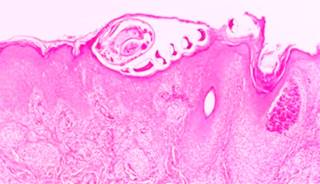

Se trata de masculino de 29 años con lesiones nodulares pruriginosas en piel de brazos, abdomen y piernas. Se le realizó biopsia de antebrazo izquierdo con diagnóstico clínico de foliculitis eosinofílica. El diagnóstico histológico corresponde a infección por Sarcoptes scabiei (escabiasis). En las imágenes histológicas se identifica piel con un túnel localizado en el estrato córneo de la epidermis (Figura 1); en el fondo del túnel se ubica un ácaro con cuerpo oval y espinas en su exoesqueleto (Figura 2). En el trayecto hay presencia de huevos en diferentes estadios de maduración (Figura 3). La dermis cuenta con un infiltrado inflamatorio mixto y en los folículos pilosos hay cúmulos de eosinófilos, lo que corrobora la impresión clínica de foliculitis eosinofílica secundaria a infección por ácaros (Figura 4). La escabiasis tiene diversas formas de contagio, pero en todas se incluye el contacto directo. Las principales manifestaciones clínicas incluyen prurito y lesiones lineales entre los pliegues y dedos correspondientes a los túneles. El ciclo de vida de los microorganismos comienza cuando la hembra deposita los huevos en la epidermis, tardando de tres a cuatro días para convertirse en larva, de 10 a 14 en madurar y después de este tiempo transportarse a través de la epidermis.

Figura 1: Túneles en el estrato córneo de la epidermis que contienen ácaros y huevos (porción superior); la dermis presenta infiltrado inflamatorio (porción inferior).